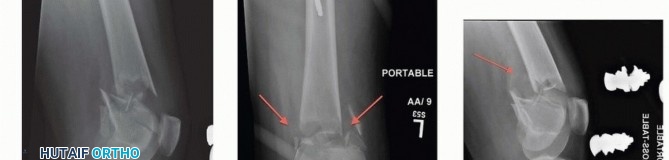

### FIG 3 • A. Patient with a grade IIIA open distal femur with extruded fragment; the “extension” of the femoral condyles is outlined. B. Patient with a distal femur fracture with intercondylar extension showing the subtle rotational deformities of the individual condyles. C. The muscle forces are shown on the distal femur, as is the femoral artery and vein entering the canal of Hunter (arrow). The adductor magnus inserts on the adductor tubercle, leading to a varus deformity of the distal segment. D. A lateral image of the same patient with the popliteal artery and tibial nerve drawn in to show the relative proximity to the fracture ends. 468

### FIG 4 • A,B. Coronal and sagittal CT angiography images showing intact femoral artery in a severely comminuted distal femur fracture (red arrows). Dedicated knee films should always be obtained in the assessment of distal femur fractures. Additionally, the entire femur, to include the hip and knee, should be imaged to look for possible extension and associated injuries and to allow for preoperative planning ( FIG 5). In cases of severe comminution, radiographs of the contralateral knee can aid in preoperative planning as well. A dedicated CT scan is an important adjunct to the preoperative planning when there is articular involvement ( FIG 6). Generally, extra-articular distal femur fractures do not require a CT scan. However, it has been shown that coronal fractures may be missed on plain films, and thus there is a low threshold for obtaining a CT scan for fractures of the distal femur. 11 If the fracture pattern warrants a temporary bridging external fixator, it is best to obtain the CT scan after placement of such a fixator for better definition. Coronal and sagittal reconstructions should be requested. Three-dimensional images can be created from most CT scans. This can also aid in the preoperative planning ( FIG 7A,B). Subtle sagittal plane rotational malalignment between condyles can be assessed ( FIG 7C). If associated soft tissue injury is suspected, such as ligamentous tears or tendon ruptures, then magnetic resonance imaging (MRI) may be indicated. Routine use of MRI, however, is not needed. ## DIFFERENTIAL DIAGNOSIS Proximal tibia fracture Femoral shaft fracture Septic knee Patella fracture Anterior cruciate ligament rupture Knee dislocation ## NONOPERATIVE MANAGEMENT There are few relative indications for nonoperative management of distal femur fractures: Poor overall medical condition Patient has severe comorbidities and is too sick for surgery. Patient has extremely poor bone stock. Spinal cord injury (paraplegia or quadriplegia) Some special situations may warrant nonoperative care on case-by-case basis. Nondisplaced or minimally displaced fracture Select gunshot wounds with incomplete fractures Extra-articular and stable Unreconstructable Lack of experience by the available surgeon or lack of equipment or appropriate facility to adequately treat the injury. Transfer is indicated in these situations; otherwise, nonoperative treatment may be the only option. There are several methods for nonoperative treatment. Skeletal traction Cast bracing Knee immobilizer Long-leg cast There are acceptable limits for nonoperative management: Seven degrees of varus or valgus Ten degrees of anterior or posterior angulation. A flexion deformity is less well tolerated than an extension deformity. Up to 1 to 1.5 cm of shortening Two to 3 mm of step-off at the joint surface 469